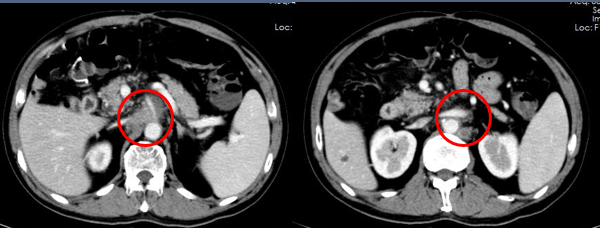

影像评估(2周期):

2019.06.29

2019.08.16

影像评估(4周期)

2019.10.21